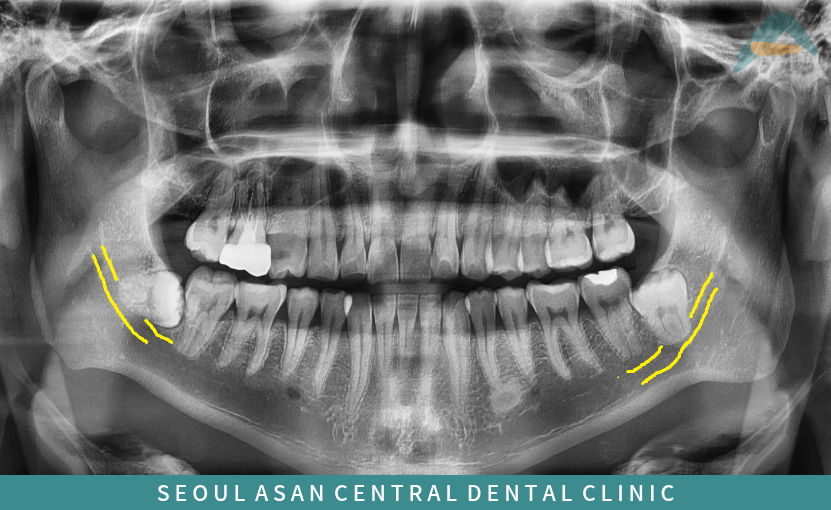

수정구치과에서는 발치를 진행하기 전

파노라마 사진과 3D CT 촬영을 통해

치아 뿌리 끝부분과

아래턱 하방으로 지나가는

하치조 신경과의 거리를

면밀하게 파악하는 과정을

거치는게 필요한데요.

아래턱 하방에는

감각과 자극을 느끼고 감지하는

큰 신경관인

하치조 신경이 지나가고 있는데

발치 시 이 신경을 건드리게 된다면

주변으로 감각이 무뎌지거나

찌릿한 느낌이 들 수도 있으며

심한 경우 마비가 오는 등

여러 가지 부작용이 생길 수 있기 때문에

발치 시 주의를 하여야 합니다.